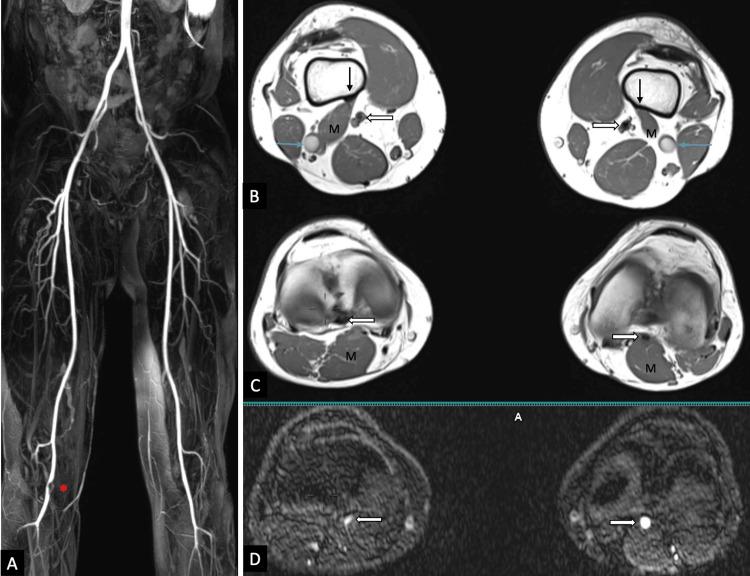

Imaging Findings and Management Strategy in Type II Popliteal Artery Entrapment Syndrome: A Tale of Two Cases.

Popliteal artery entrapment syndrome (PAES) is a frequently underdiagnosed condition that should be investigated in adults who experience exertional intermittent claudication in the lower limbs. If detected early, it is a surgically treatable cause of leg claudication in young individuals. PAES can be inherited or acquired through muscular hypertrophy, and the literature classifies it into six categories (I-VI) based on anatomical type. We intend to report the magnetic resonance imaging (MRI) findings of two cases with type II PAES and their management.